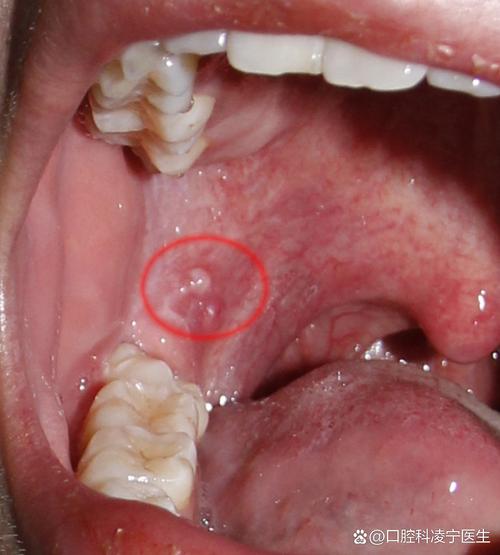

口腔白斑

(图片来源网络,侵删)- 外观:表现为口腔黏膜上不能被擦除的白色斑块,形态不一,可为平的、皱纸状的、颗粒状的或疣状的,质地较硬,界限清晰。

- 特点:这是最需要警惕的情况之一。 白斑本身是一种癌前病变,虽然大部分白斑终身不变,但有少数可能发生癌变。尤其是出现以下情况时,癌变风险增高:

- 白斑表面出现粗糙、硬结、溃疡或出血。

- 白斑基底变硬。

- 白斑面积迅速增大。

- 伴有明显疼痛或麻木感。

- 高危因素:长期吸烟、嚼槟榔、酗酒是主要诱因。

扁平苔藓

- 外观:表现为口腔黏膜上出现白色、灰白色的条纹、网状或环状花纹,有时也可见到丘疹或水疱,常见于颊黏膜、舌、牙龈等处。

- 特点:这是一种慢性炎症性自身免疫性疾病,部分患者的口腔扁平苔藓有癌变风险(约1%-5%),尤其是糜烂型、萎缩型和长期不愈的类型,常伴有口腔黏膜粗糙、烧灼感、刺激痛等症状。